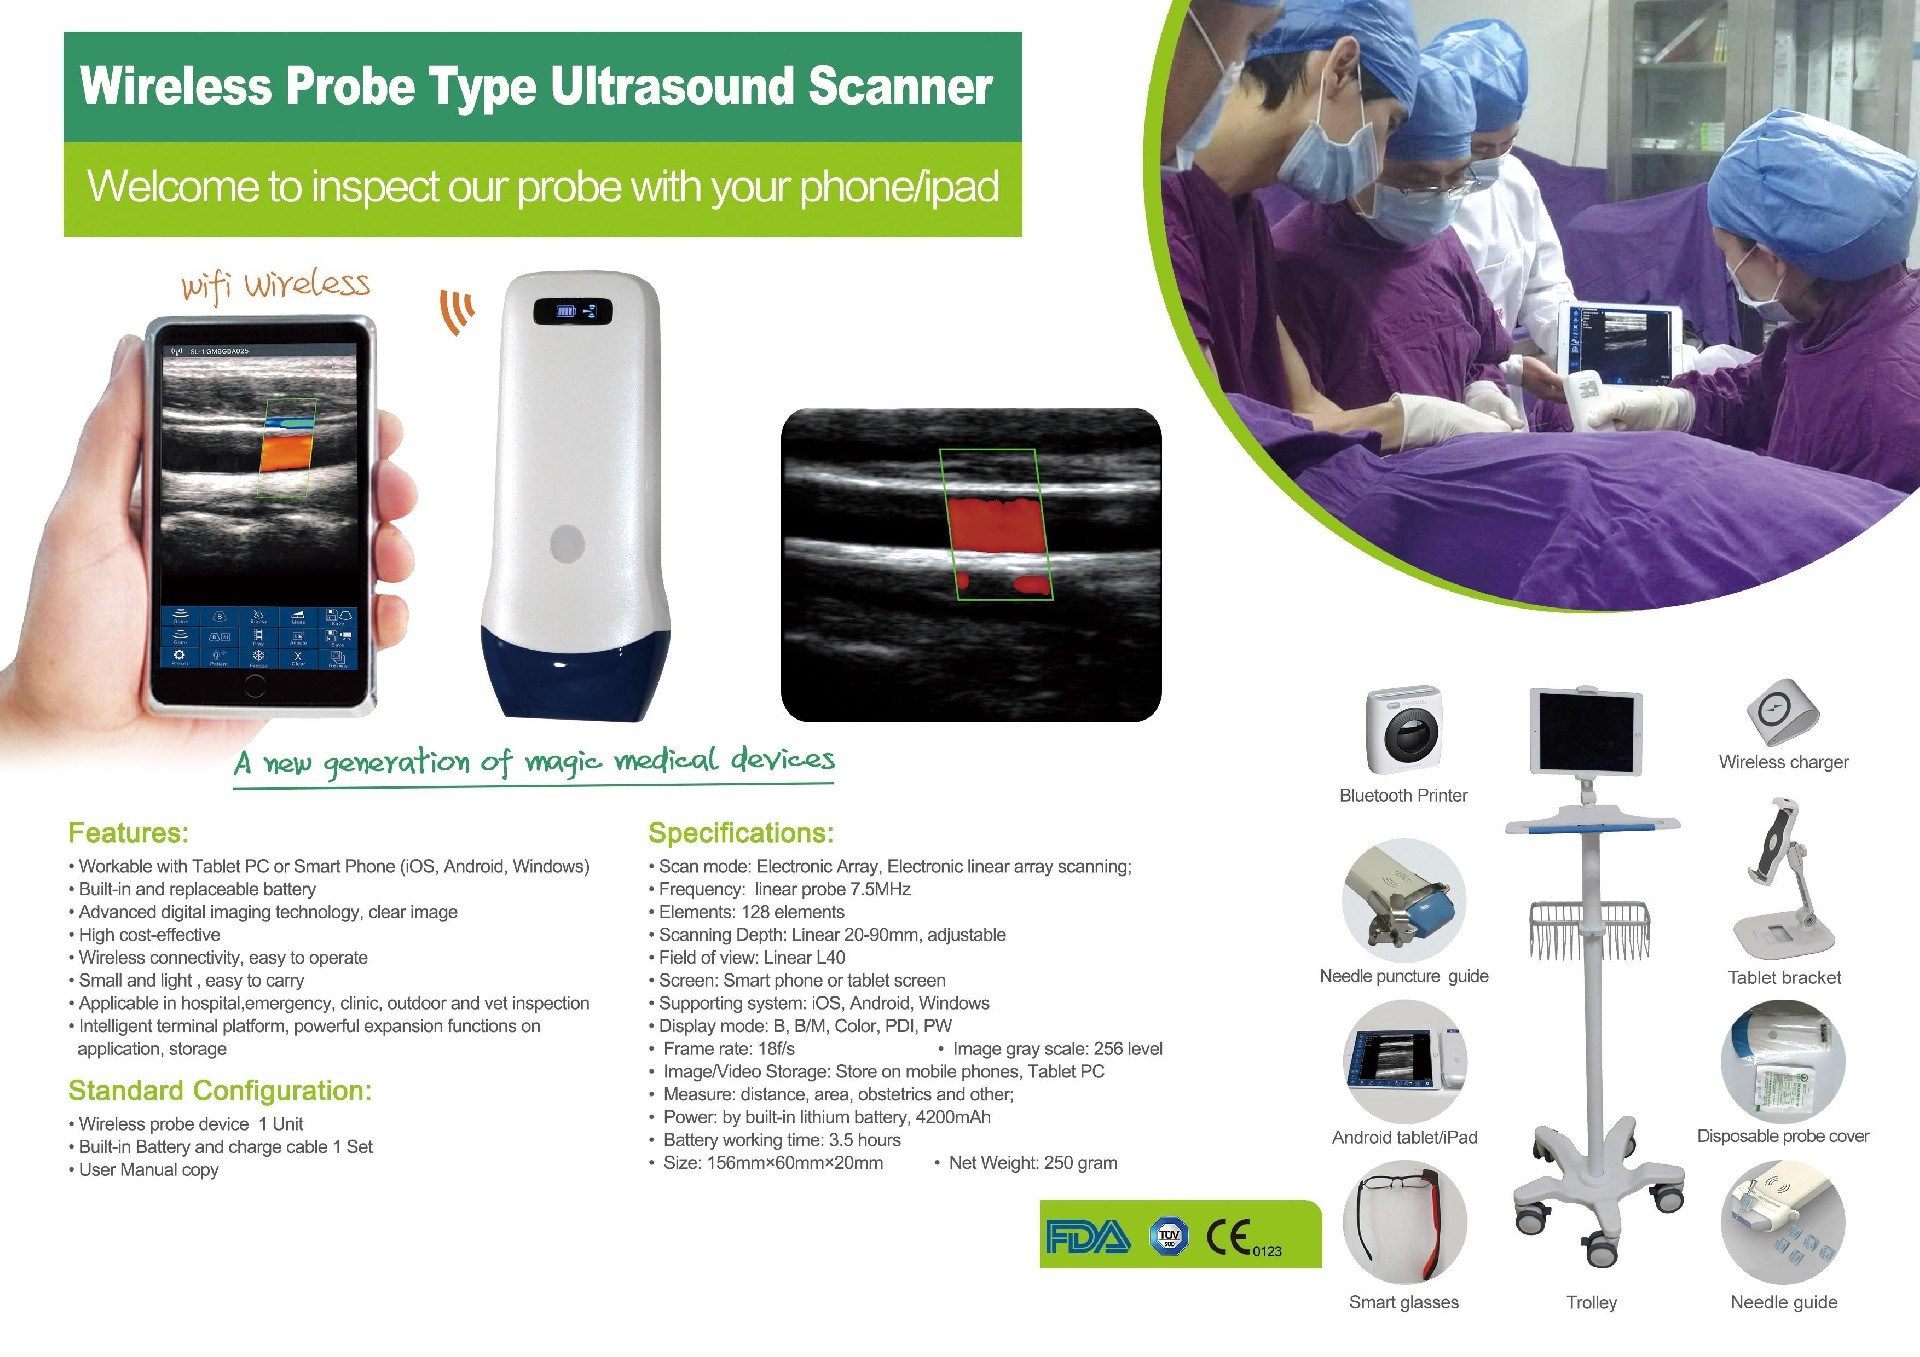

It is a multi-function CP5L micro linear ultrasound probe.

Iphone / Android ultrasound probe

Product Configuration for wireless USB ultrasound probe:

Standard Configuration :Wireless Ultrasound Scanner x 1 unit USB Charging Cable x 1pc

Optional: Carrying Bag or Aluminium Suitcase ,Stainless Steel Puncture Guide ,Android or iOS Phone/Tablet ,Windows PC,Wireless Power Bank ,Tablet Bracket,Trolley .